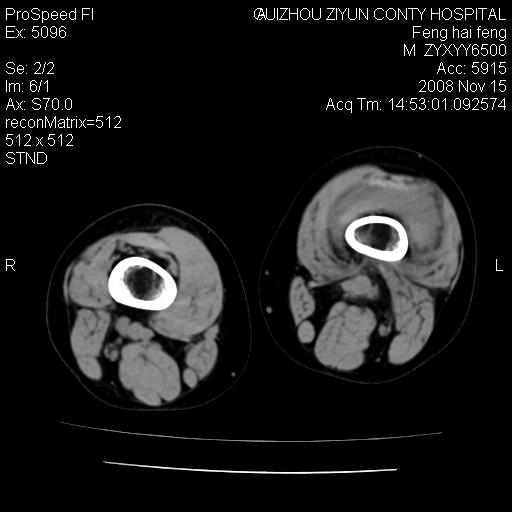

标题: CT16656:M 14Y 左膝关节肿胀一年余。其余病史不详。 [打印本页]

标题: CT16656:M 14Y 左膝关节肿胀一年余。其余病史不详。

考虑左侧髌骨结核;左膝关节滑膜肿胀、增厚,关节囊积液。

左膝滑膜型关节结核可能性大!支持!滑膜型关节结核主要ct表现:关节囊肿胀,积液,关节面见小破坏灶,并见点状死骨!

好大的左腿!考虑左侧髌骨结核,左膝关节滑膜肿胀、增厚,关节囊积液。

左侧髌骨结核;左膝关节滑膜肿胀、增厚,关节囊积液